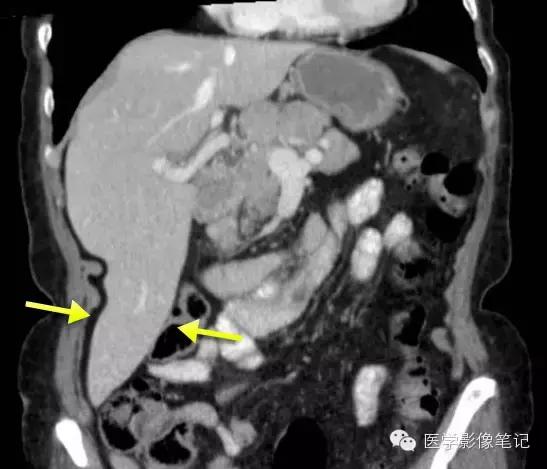

肝脏变异

獭尾肝/包围肝,见于5%的成人。

獭尾肝/包围肝

利德尔叶(Riedel’s Lobe)

肝的右下部向下如舌状突出生长的舌叶。

乳头状突

肝尾状叶结构,常误认为肿大淋巴结。

肝左叶缺如

右叶发育不全

内脏反转

咳纹肝

女性多见,由慢性咳嗽膈肌紧勒肝脏所致,也可见于过度束腰的妇女。

镰旁肝假病灶

多位于左叶内侧段或(和)左叶外侧段前缘镰状韧带旁。

机制:1、镰旁肝局部特殊血供因素;2、镰旁肝局部脂肪浸润。

来源:医学影像笔记